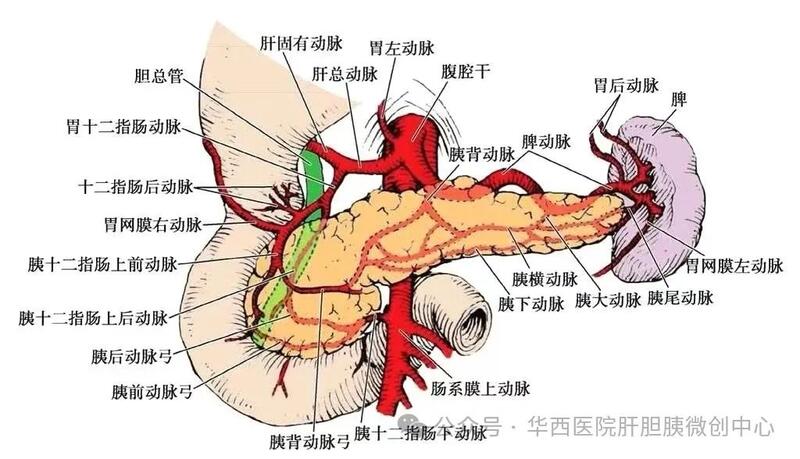

脾脏的解剖

1, 脾实质富含血窦,质地脆,对于切除中的出血控制是第一大难点,也是手术失败的主要原因。脾脏部分切除至少要保留25%以上血供良好的脾脏体积方能维持脾脏的功能。

2, 脾的解剖位置:“深藏”在左上腹,腔镜下暴露和操作空间有限。

3, 脾肿物精确定位:术前需要充分的影像学评估以及术中超声协助定位。